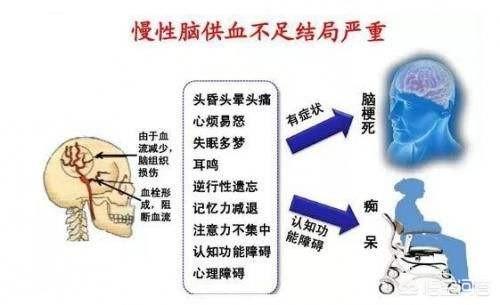

大脳の血液供給不全は、高齢者ではあまりにも一般的だが、最近では30歳以下の若者でも珍しくない。文献を見ると、60歳以上の3分の2、80歳以上の80%に慢性的な低灌流が起こっている。しかし近年、頚椎症による脳血流不全に悩む若者が増えている。重篤な脳循環不全は、脳梗塞や認知症などの重篤な疾患につながることもあり、注意が必要です。

慢性脳虚血とは、一般に慢性脳虚血と呼ばれ、脳への血液供給が様々な原因で慢性的かつ広範囲に不足し、脳の虚血や低酸素状態を引き起こし、一連の脳機能障害を引き起こす臨床疾患である。慢性脳虚血はもともと中高年に多い疾患であり、統計によれば中高年の2/3が慢性脳虚血に罹患しているといわれている。しかし、近年は若年化する傾向にあり、これは若者の不健康な生活習慣と密接な関係がある。

慢性的な脳機能不全は多くの臨床症状を呈し、そのほとんどは弛緩性である。

最も一般的で見過ごされやすい臨床症状は以下の通りである:

めまいと頭痛。めまいと頭の鈍さ、心の不明瞭さ、頭の腫れと痛み、頭の鈍さと痛み、めまいと立ちくらみ、めまいと難聴などである。

不眠または眠気。不眠症や夢見がち、眠りが浅く目が覚めやすい、一日中眠い、食後に眠くなるなどである。

記憶喪失。例えば、最近あったことを思い出せなかったり、よく使う電話番号やよく知っている名前を思い出せなかったりする。目の症状。目の腫れや痛み、目を開けるのが億劫になる、目がかすむなど。

⑤ 耳症状。耳鳴り、耳の「閉じこもり」、難聴。

(vi) バランス障害。不安定な歩行、ゆっくりとした歩行、弱々しい態度などとして現れる。

(vii) キャラクターの変更。例えば、引っ込み思案になったり、寡黙になったり、無関心な表情になったり、おしゃべりになったり、イライラしたり、頑固でわがままになったりする。一過性の意識障害や精神状態の悪化、正常な判断力を失う人もいるが、これらはすべて脳への血液供給不足が関係している。